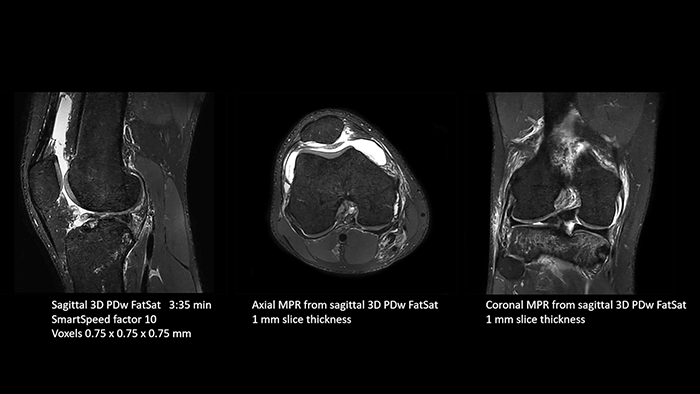

Previously, the practice wasn’t able to use 3D imaging on all joints, because the time required was too long, and on some joints it was simply not possible to achieve a good quality image, Dr. Schröter says. “Now, with SmartSpeed we consistently use 3D imaging for all joints and can thus discover the smallest changes, for example in the cartilage. And that, of course, helps us in making a detailed diagnosis.”

Dr. Schröter says their MSK images show high contrast and extremely high quality. He mentions the menisci as an example. “We use a 3D proton density weighted fatsat sequence, thickness is 0.3 mm and scan time 3 minutes. The MPRs show an unbelievable resolution. Very small tears and even fraying of the tip of the meniscus become visible, which is normally only possible in arthroscopic surgery.

With these 3D scans we can create freely selectable MPRs that are pin-sharp, allowing us to easily see pathological changes.”